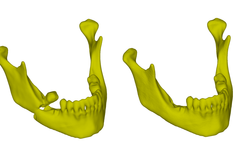

- Dzięki zastosowaniu modeli żuchwy wykonanych przy użyciu druku 3D, znacznie skrócono czas przeprowadzenia zabiegu chirurgicznego, a także zminimalizowano wystąpienie komplikacji śródoperacyjnych - wyjaśnia twórca modelu dr inż. Paweł Turek, adiunkt w Katedrze Technik Wytwarzania i Automatyzacji PRz. - Dodatkowo opracowano procedurę umożliwiającą komputerowe (wirtualne) odtworzenie geometrii żuchwy sprzed wystąpienia urazu.

Obecnie prowadzone są badania usprawniające proces segmentacji i rekonstrukcji obszaru sklepienia czaszki oraz oceny dokładności wykonania małych i skomplikowanych obiektów na przykładzie trzonów i koron zębów.